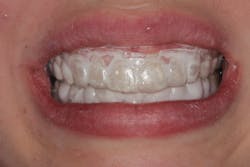

Remin Pro was then applied to the teeth with a gloved finger, and the bleaching trays containing Remin Pro were put into place (figure 5). The patient was instructed to wear the trays daily for at least 30 minutes, with longer being better. The goal of using the chemotherapeutic cream was to remineralize the white spots in a minimally invasive way now that the enamel pores were wide-open.